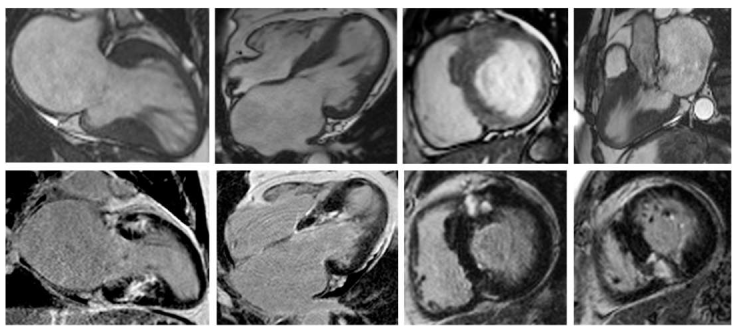

Nonetheless, due to increased temporal resolution, ability to comprehensively evaluate all heart structures and capacity to characterize myocardial tissue and unravel fibrosis, CMR has currently became the gold-standard imaging tool for diagnosing and assessing patients with HCM. CMR is able to accurately quantify heart chambers’ volumes and dimensions and also both LV and right ventricle (RV) systolic functions. Moreover, CMR is the only large-scale available noninvasive imaging tool capable of tissue characterization. This aspect has a tremendous role in patients with HCM since it can identify and accurately quantify both myocardial replacement and diffuse fibrosis and it can also exclude other infiltrative cardiomyopathies such as amyloidosis [27]. CMR summarized in Table 1. Specific cases of HCM assessed by CMR are presented in Figure 2, Figure 3 and Figure 4.

Figure 4. Contrast-enhanced CMR in a 50-year-old female patient with a history of hypertrophic cardiomyopathy with LV apical aneurysm (from the own collection of the authors). (Upper row): b-SSFP cine images in four, three and two chambers, and short axis, respectively. The LV is dilated (110 mL/m2) with severely impaired systolic function (LVEF 25%). There is asymmetrical LV hypertrophy with a maximum wall thickness of 28 mm at the level of the interventricular septum. Note the large apical aneurysm with a maximum diameter of 40 mm and thin walls. (Lower row): LGE imaging shows transmural fibrosis of the LV apical aneurysm and a small focal intramyocardial scar at the level of the basal infero-lateral wall. The total percent of fibrosis is 16% of the LV myocardium. No thrombus is seen inside the apical aneurysm. Abbreviations: b-SSFP, balanced steady-state free precession; CMR, cardiac magnetic resonance imaging; LVEF, left ventricle ejection fraction; LGE, late gadolinium enhancement; LV, left ventricle.